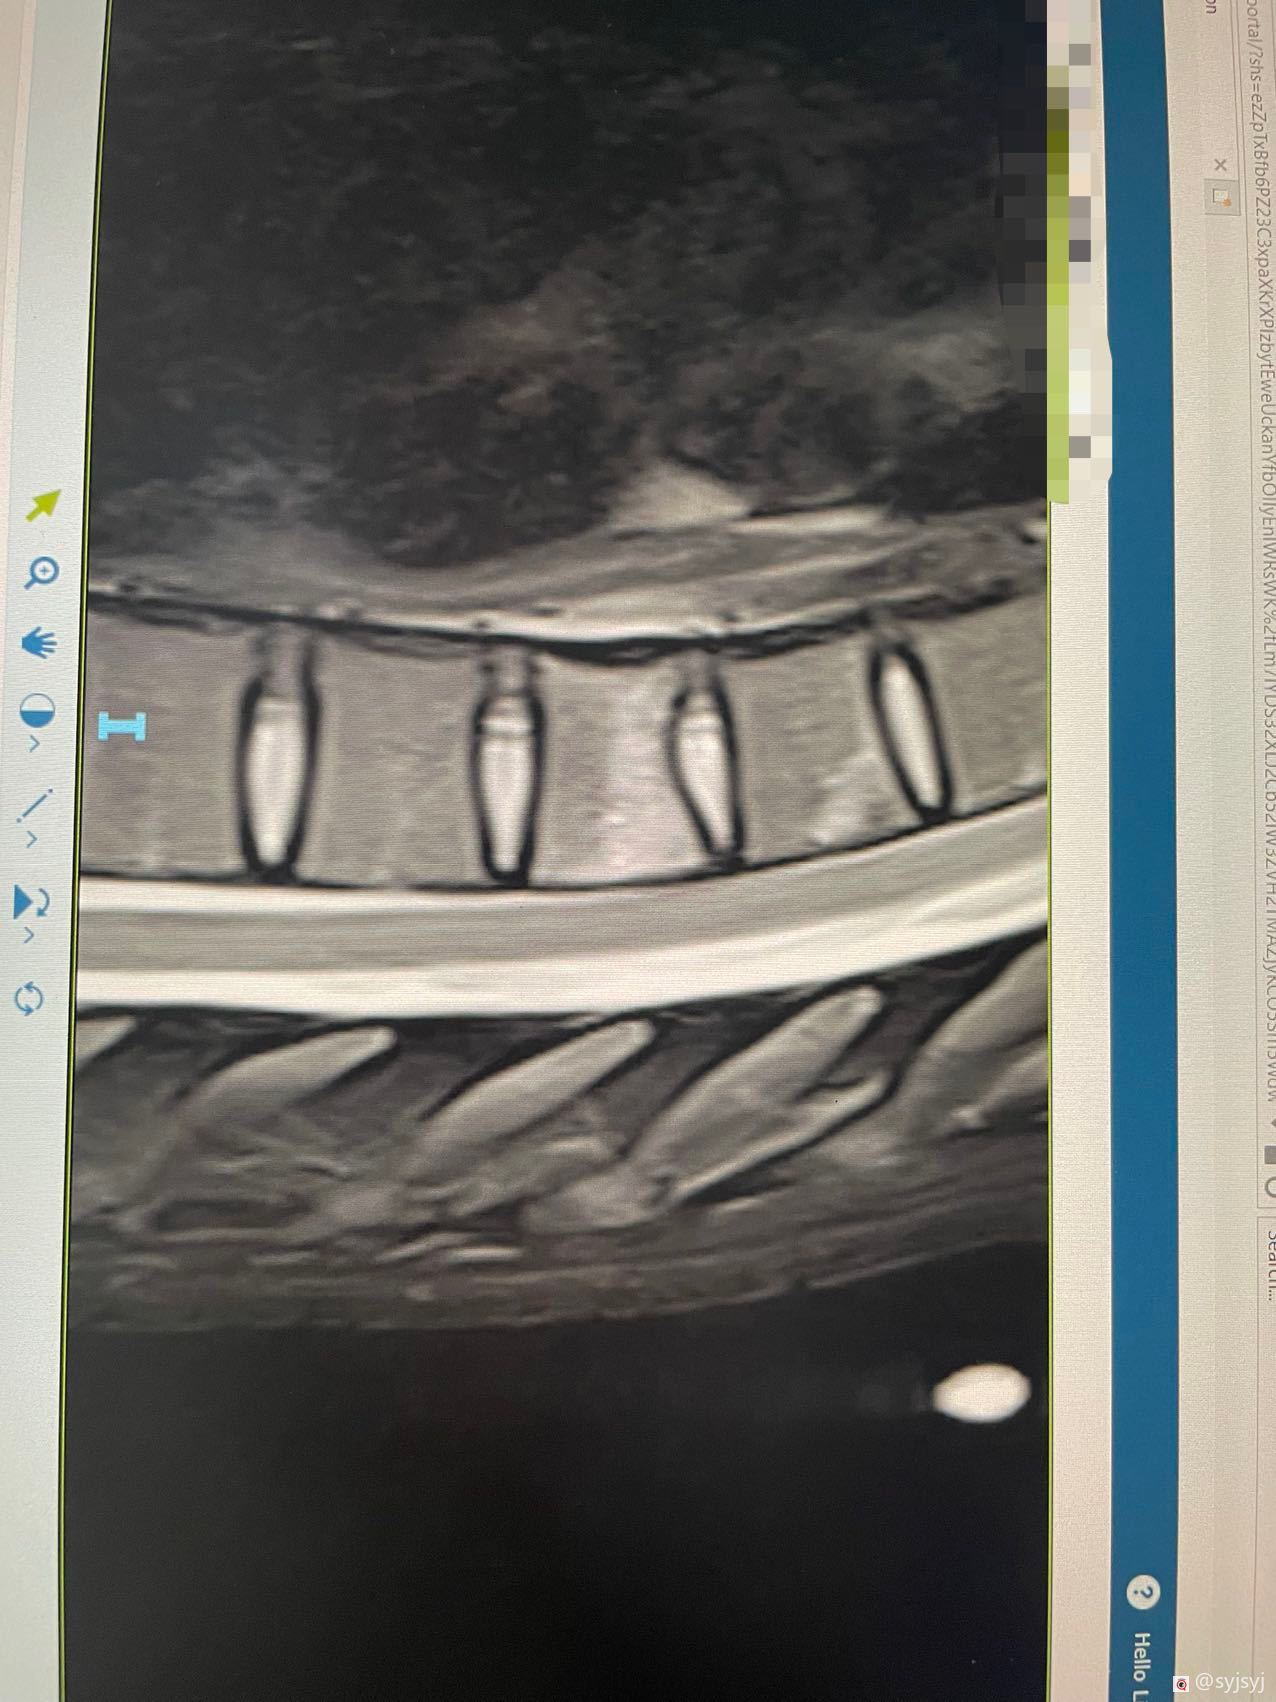

我在1月22号下午遇到了一个摩托车车祸,当时的车速是很快的至少60多码,很不幸的是我飞了出去然后落在了草丛岩石上,当时我是完全不能动弹的,我的右半边身体已经麻木没知觉,除了大面积的擦伤,我的右肩胛骨骨折,手腕背部严重割伤,脊柱第7节压缩。

这些是我伤情的报告:

其实右手臂的伤还不止这些,还有左边也有一些伤,不过右边最严重。